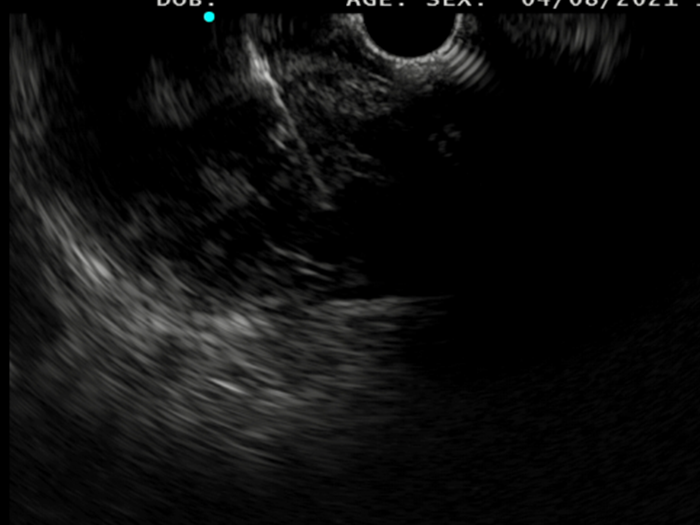

Saul was consented to move forward with an EUS-guided FNB, that was performed with Acquire™ S. This allowed his gastroenterologist to further assess the lesion. A 51.9 x 47.9 mm hypoechoic, inhomogeneous lesion, which appears hypervascularised on Hi Flow, is observed. Unfortunately, an advanced, unresectable GIST is still suspected.​